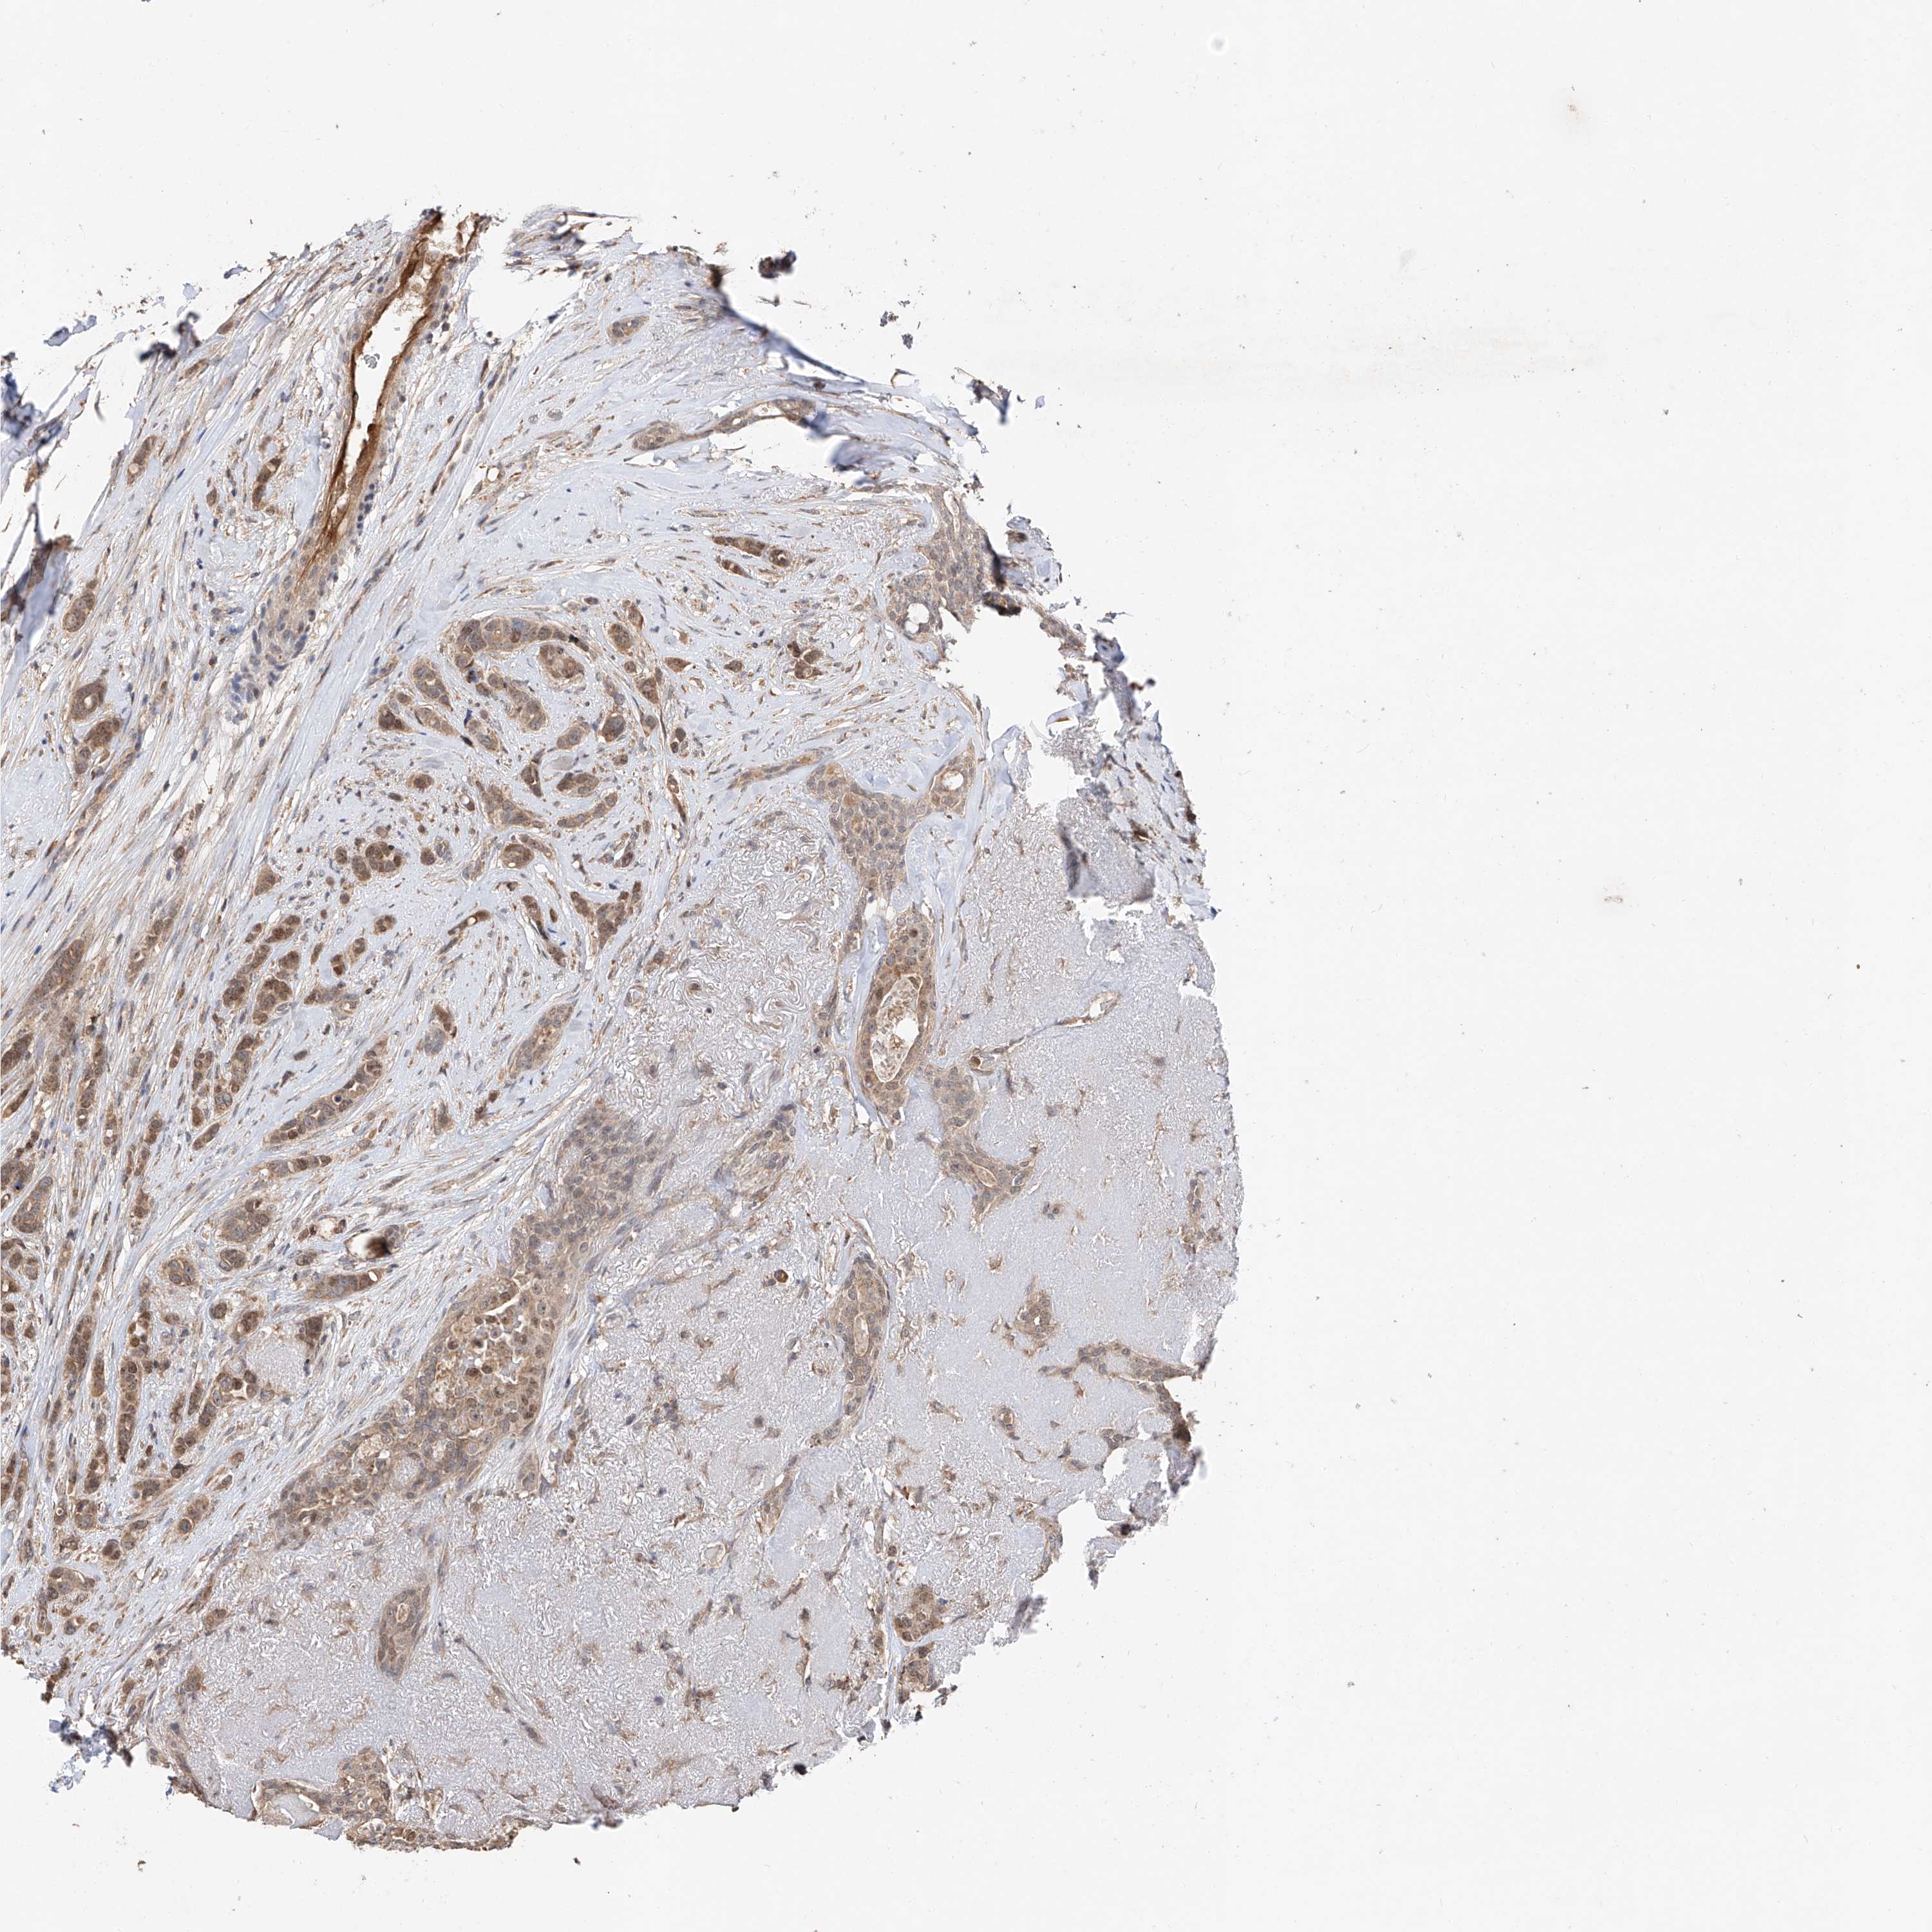

Breast cancer

Human cancer